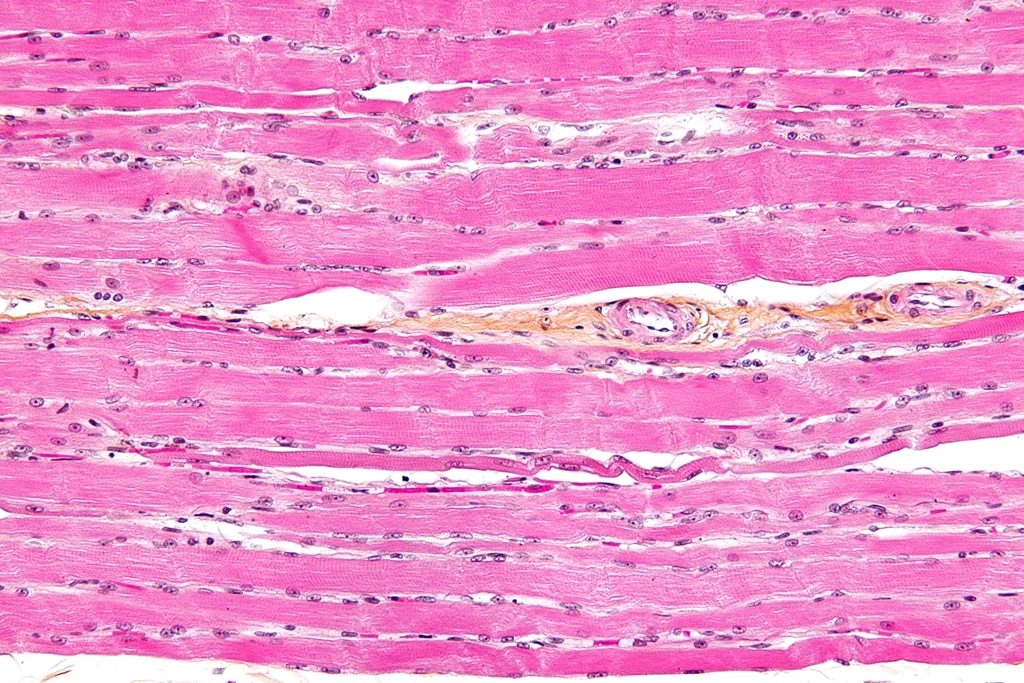

횡문근의 현미경 사진 (출처 : 위키미디어)

참고로 횡문근(Striated muscle)은 가로무늬 근육이라고 불리기도 하는데, 주로는 골격근에 부착되어 대부분 의지적으로 움직일 수 있는 근육을 말합니다. 이런 횡문근이 융해(녹는다) 되어 나타나는 증상을 말 그대로 “횡문근+융해+증”, 횡문근융해증이라 부르는 것입니다